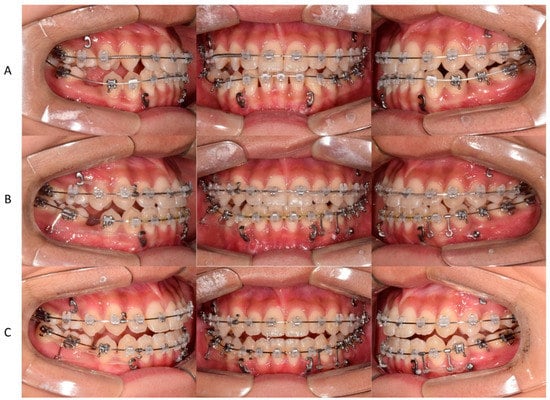

In the second phase, after bonding the fixed appliance to the maxillary and mandibular dentition, treatment started with the following goals: proclining maxillary incisors and closing most of the extraction space of the extracted mandibular primary tooth through protraction of the right molar, which induced spontaneous eruption of the right third molar (Figure 4). In addition, to improve the midline, the mandibular left third molar was extracted, and the mandibular dentition was moved to the left.

An anterior miniplate was used for protraction of the mandibular posterior molars after the extraction of the right primary second molar (Figure 5A). Since the midline of the maxillary dentition was also deviated to the left, total arch distalization was performed towards the right side of the maxillary dentition using the miniplate on the right side of the maxilla to improve the midline. A miniscrew was placed on the left side of the mandible, and distal movement of the dentition was performed to correct the midline and improve the occlusal relationship in the posterior region.

Figure 5. Nonsurgical orthodontic treatment process using a fixed appliance. (A) space regaining for maxillary right lateral incisor arrangement after bonding the fixed appliance. (B) Closing the mandibular extraction space using the miniplate anchorage, moving the maxillary midline to the right, and moving the mandibular midline to the left. (C) The mandibular extraction space was closed.